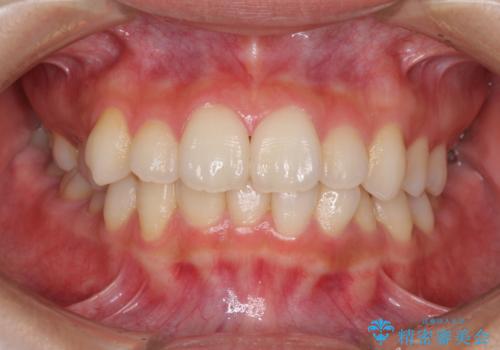

- 前歯のデコボコを気にして来院された患者様です。

叢生と捻転が随所に認められるものの、マウスピースで十分対応可能であったため、インビザラインにて矯正治療を行うこととしました。

マウスピース矯正は毎日しっかりと装着することがとても大切です。

こちらの方はしっかりと指示を守って装着してくださったため、予定通り治療を終えることができました。